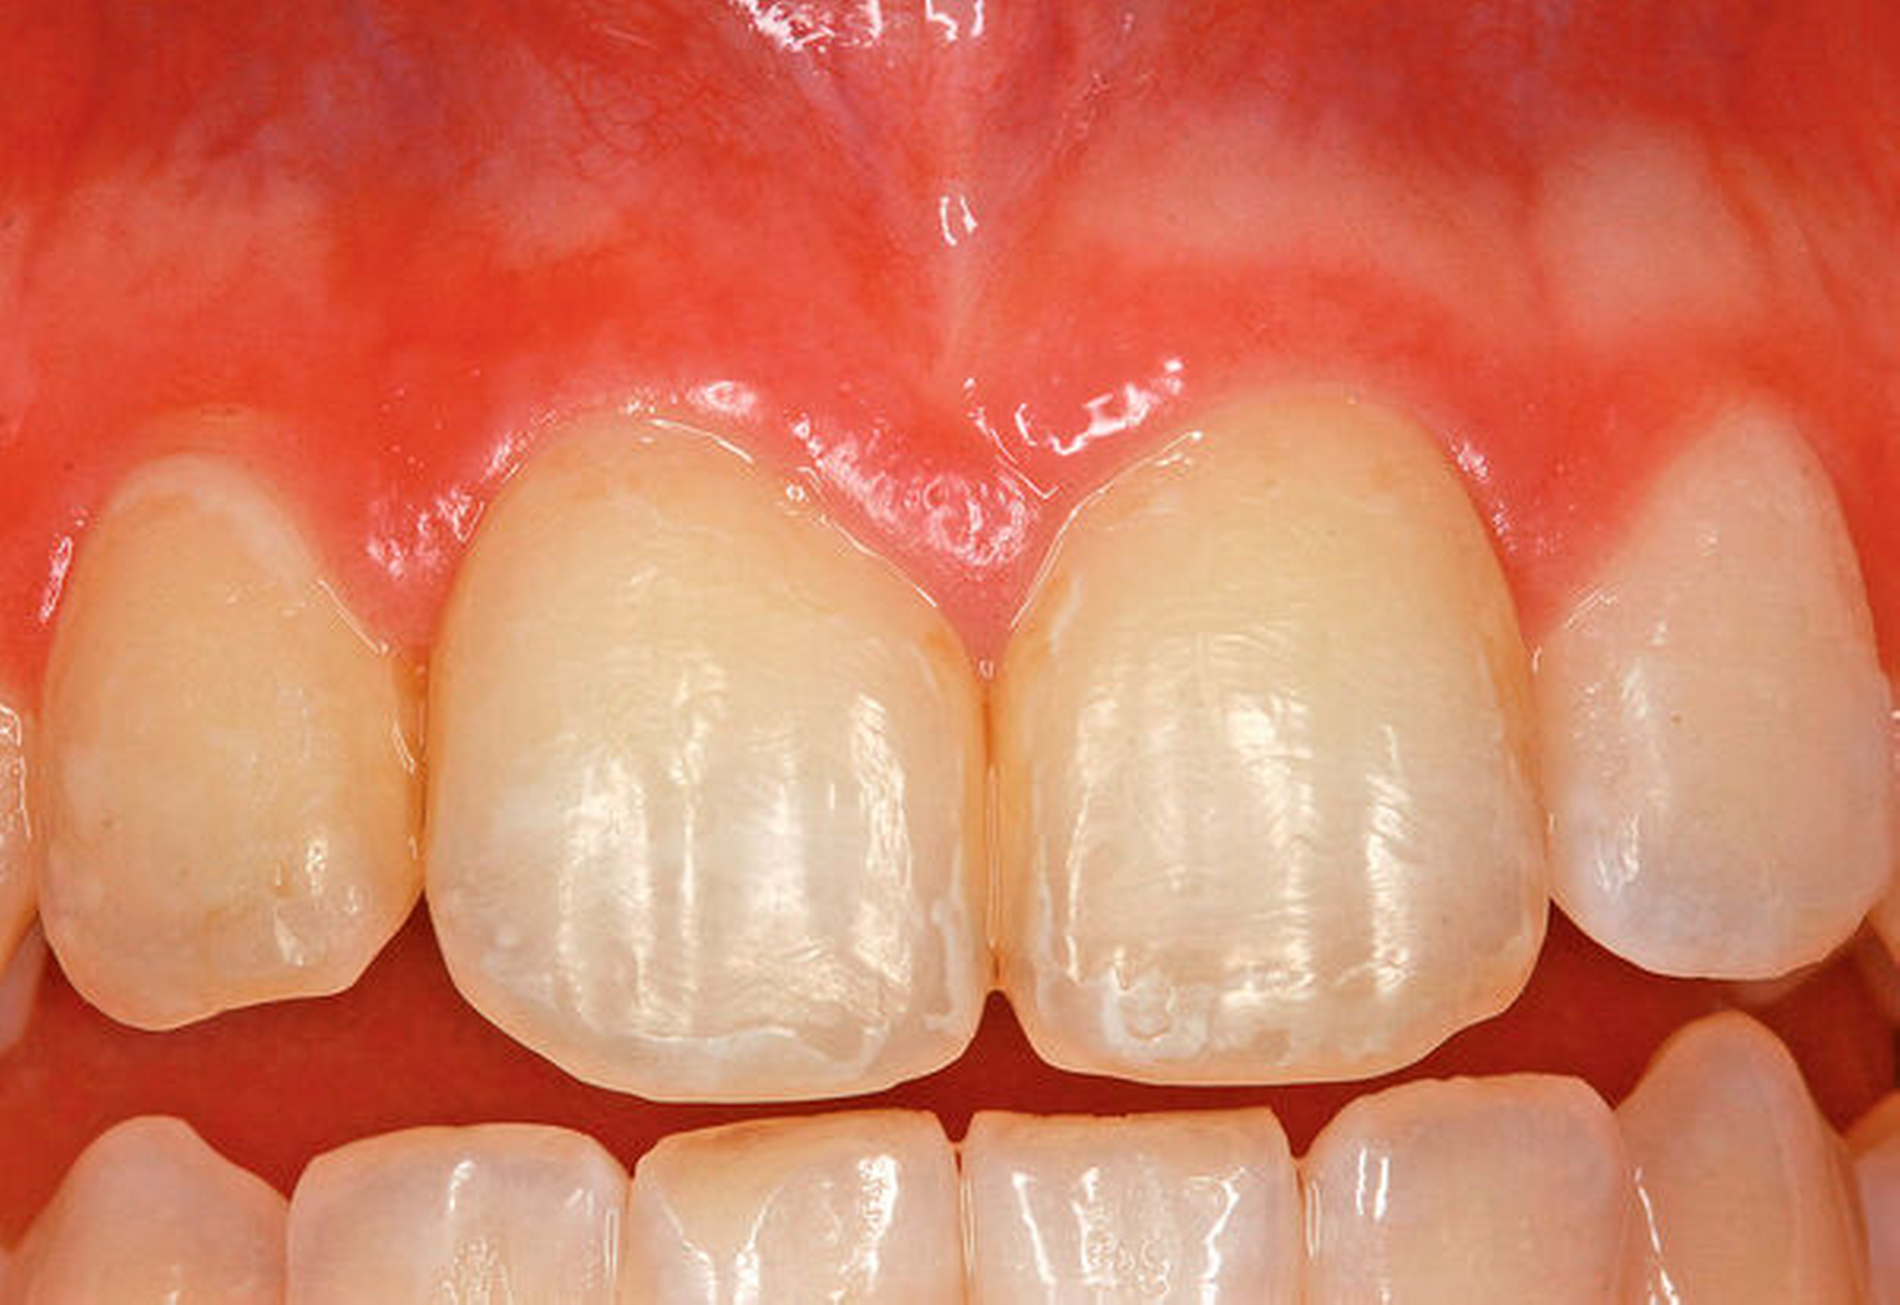

In der fünften postoperativen Woche konnte die dentale Schienung durch den Hauszahnarzt entfernt werden und die replantierten Zähne wiesen keinen Lockerungsgrad auf. Nach zehn Wochen war die Patientin unverändert beschwerdefrei, wobei sie ein minimales Zahnlockerungsgefühl an 11 angab. Klinisch war dies allerdings nicht zu verifizieren. Auch die Gingiva zeigte klinisch einen regelrechten Befund (Abbildung 7).